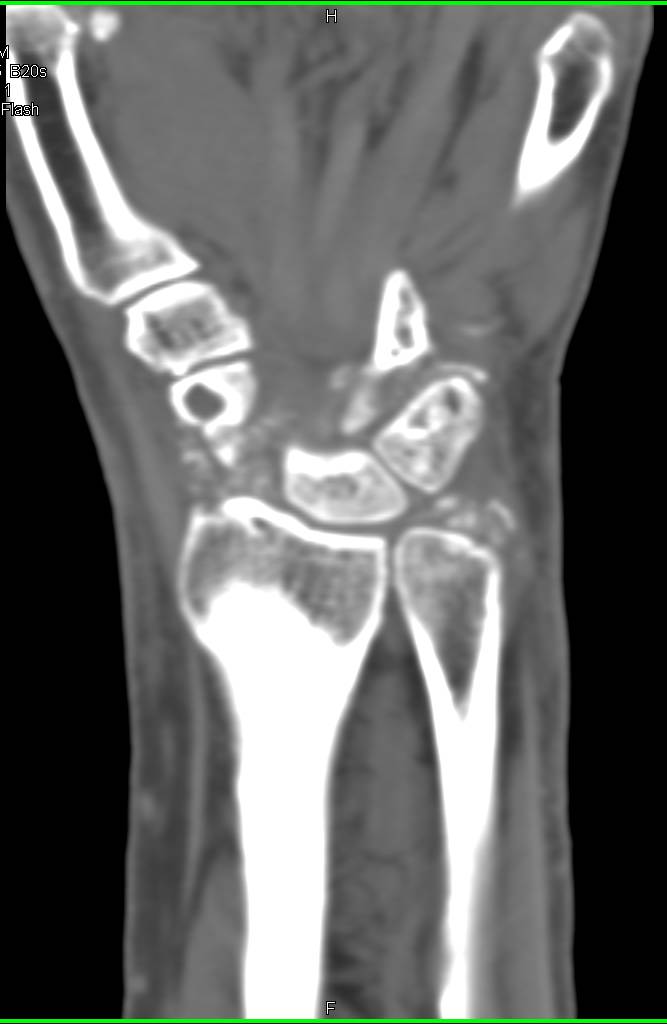

Diagnosis

Recurrent Renal cell Carcinoma Metastatic to the Adrenal and Ribs